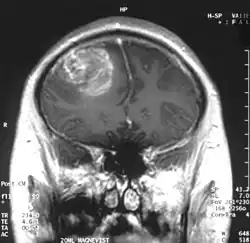

Die Diagnose wird zunächst durch bildgebende Verfahren wie Computertomographie (CT) oder Magnetresonanztomographie (MRT) gestützt. In der CT-Bildgebung mit Kontrastmittel erscheint das Glioblastom unregelmäßig geformt mit randständig starker Kontrastmittelaufnahme (ringförmiges Enhancement). Bei kleineren Tumoren ist dieses ringförmig konfiguriert, bei größeren bildet es eine girlandenartige Formation aus. In der Umgebung des Tumors bildet sich typischerweise ein erhebliches Ödem aus. Der MRT-Befund ist recht typisch: Die soliden Anteile des Glioblastoms reichern Kontrastmittel stark an, dagegen heben sich die Aussparungen durch zystische Anteile und die Blutungen ab. Letztendlich wird die Diagnose am Tumorgewebe, das bei einer stereotaktischen Hirnbiopsie oder Tumorresektion gewonnen wurde, neuropathologisch bestätigt. Im Einzelfall werden Supplementäruntersuchungen wie Elektroenzephalografie und Lumbalpunktion durchgeführt, die der Einschätzung der Anfallsneigung bzw. der differentialdiagnostischen Abgrenzung gegen Hirnabszesse oder Lymphome dienen.

Das Glioblastom ist durch seine inhomogene und vielfältige (daher: multiforme) Erscheinung gekennzeichnet: die Tumorschnittfläche weist häufig rötliche Einblutungen und gelbliche Gewebsuntergänge (Nekrosen) auf.